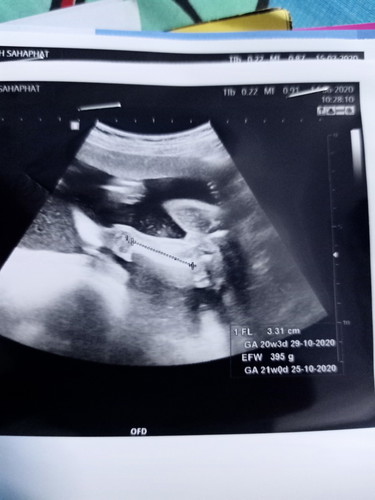

วันนี้ไปหมอมาหมอบอกว่าลูกเราน้ำหนักเกือบ400กรัม ตอนนี้ท้องได้20wคะน้องตัวเล็กหรือตัวใหญ่คะคุนแม่ๆ

บ้านนี้20w406กรัม คุนหมอบอกถือว่าปกติจ้าตามเกนฑ์ค่ะ ไม่เล็กละก็ไม่ใหญ่ค่ะ